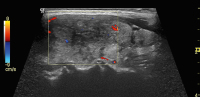

Abbildung 3: Detailaufnahme des linken Lappens zum Zeitpunkt der Erstvorstellung: im Längsschnitt das typische Muster einer subakuten Thyreoiditis de Quervain.